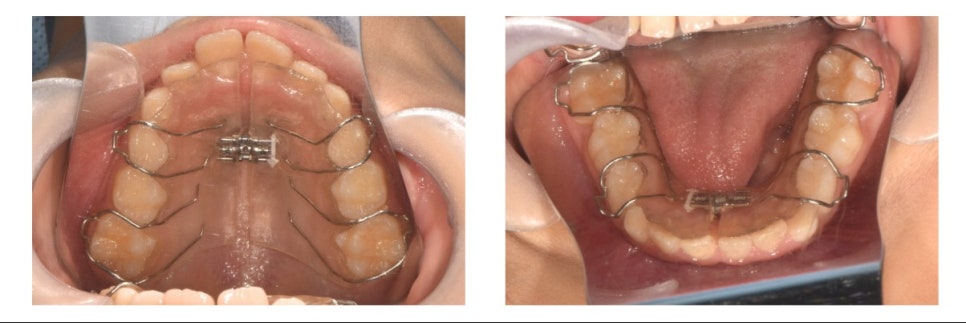

🦷 초기 치료: 공간 확보

먼저 공간을 확보하기 위해 **가철성 장치(active plate)**를 착용하였습니다.

치료 시작 3~4개월 후 구내 사진

약 3~4개월간의 확장 치료 후, 삐뚤빼뚤했던 상·하악 전치부에 공간이 생긴 것을 확인할 수 있었습니다.

이후 확장을 멈추고, 확보된 공간을 유지하기 위해 유지 장치를 제작하여 장착했습니다.